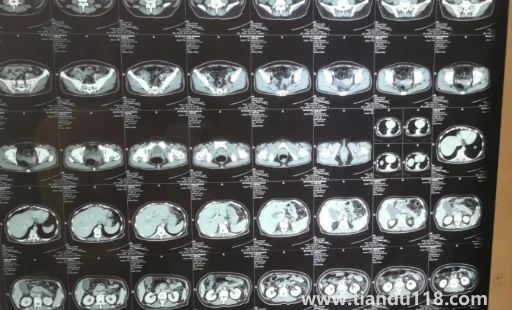

胰腺不舒服早期大便會(huì)變化嗎

胰腺患者早期大便不會(huì)有明顯影響,也有少數(shù)患者早期大便有明顯變化,如大便不暢及便秘、大便時(shí)疼痛等不適。 有的患者可能數(shù)日無大便,有的患者可能出現(xiàn)腹痛或發(fā)熱等癥狀,大便變化也沒有太嚴(yán)重。 患者應(yīng)及時(shí)就診,避免耽誤時(shí)間過長加重病情,并在醫(yī)生指導(dǎo)下服藥。 平時(shí)需要注意日常飲食和生活習(xí)慣,多注意休息,避免過度勞累。